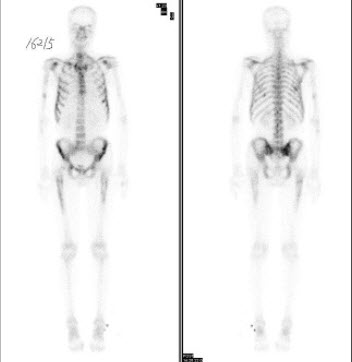

19、多项选择题

右乳癌根治术后5年,无明显不适,血清CA153正常,行全身骨显像如图,可能的诊断是()

A.多发骨转移瘤

B.骨质疏松

C.腰椎退行性改变

D.腰4、5骨转移瘤

E.大致正常的骨影像

点击查看答案